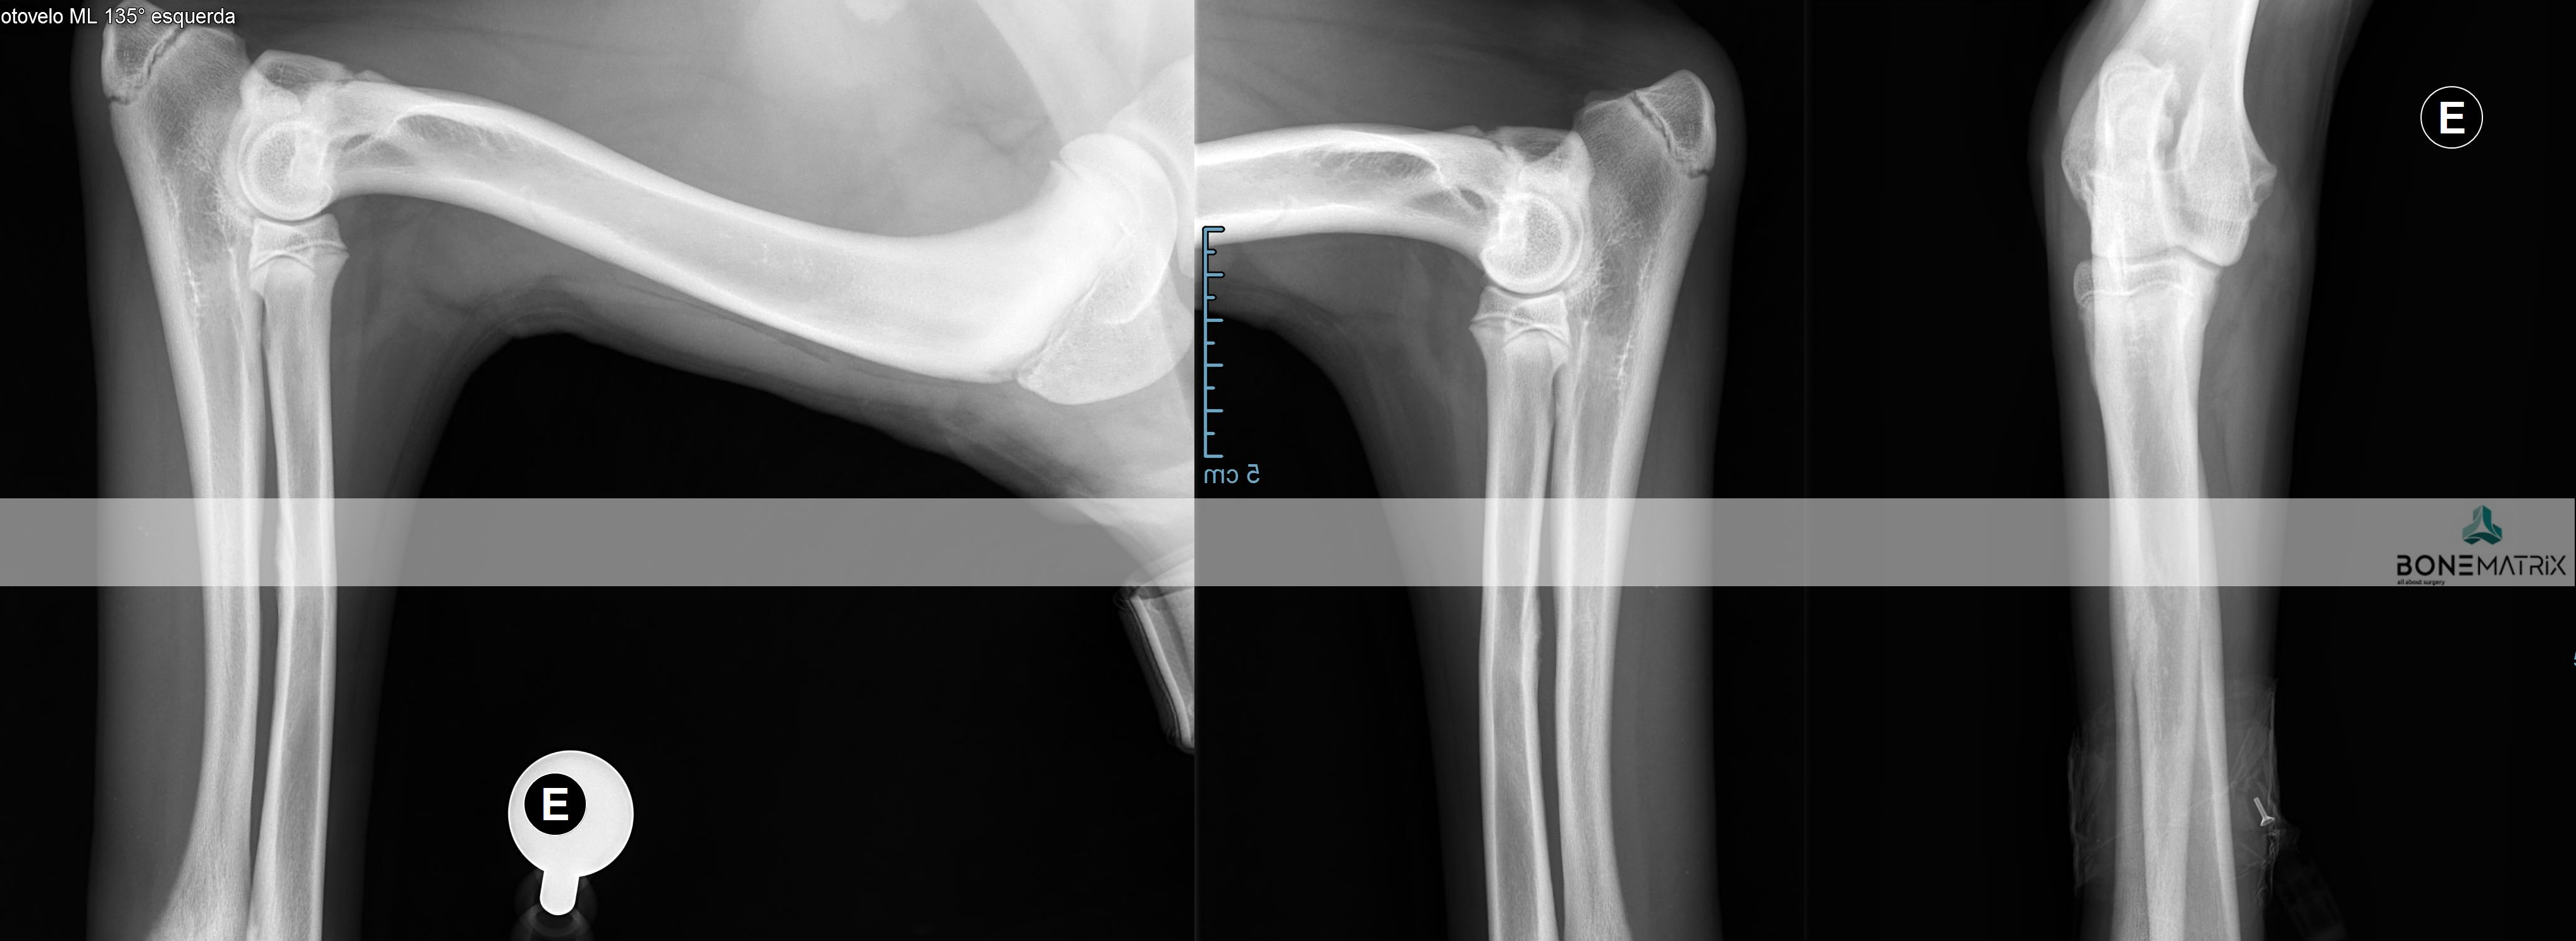

A displasia de cotovelo é uma doença de desenvolvimento caracterizada pela incongruência do cotovelo.

Dada a componente genética, frequentemente envolvida no decorrer deste processo, a patologia apresenta-se por norma bilateralmente, podendo assumir gravidade diferente em ambos os cotovelos.

A displasia de cotovelo pode assumir várias apresentações, entre elas, a não união do processo ancóneo, a fragmentação do processo coronóide, a osteocondrite dissecante, doença do compartimento medial e a incongruência per si.

Como é criada esta incongruência?

A articulação do cotovelo é constituída por 3 ossos, o rádio, a ulna e o úmero.

A incongruência do rádio resulta na apresentação deste osso mais curto que a ulna. Isto resulta num excesso de pressão sobre regiões da ulna - resulta com frequência na fragmentação do processo coronóide.

Quando a apresentação contrária ocorre, ou seja, o rádio apresenta-se mais elevado que a ulna, é exercida demasiada pressão sobre o processo ancóneo - resultando com frequência na não união do processo ancóneo.

Quando a incongruência envolve o úmero outras lesões podem ser desenvolvidas que envolvem o desalinhamento articular entre o úmero e a ulna.

A apresentação desta patologia em fases iniciais apresenta, com frequência, sinais subtis, daí a necessidade de realização de despiste de displasia de anca durante o crescimento do animal (idealmente 5 meses) para que a doença possa ser detetada antes que ocorra um desenvolvimento significativo de lesões de osteoartrite a nível intra-articular.

O diagnóstico pode ser realizado por meio de estudo radiográfico.

Contudo são indicadas técnicas de imagem avançada (tomografia axial computorizada) ou artroscopia para a realização do diagnóstico final e definição de abordagem terapêutica.